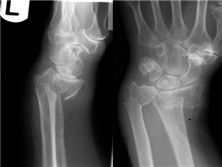

史密斯骨折

史密斯骨折好发部位与柯莱斯骨折一样,但所致畸形与柯莱斯骨折相反,其远端向掌侧移位...

X线平片